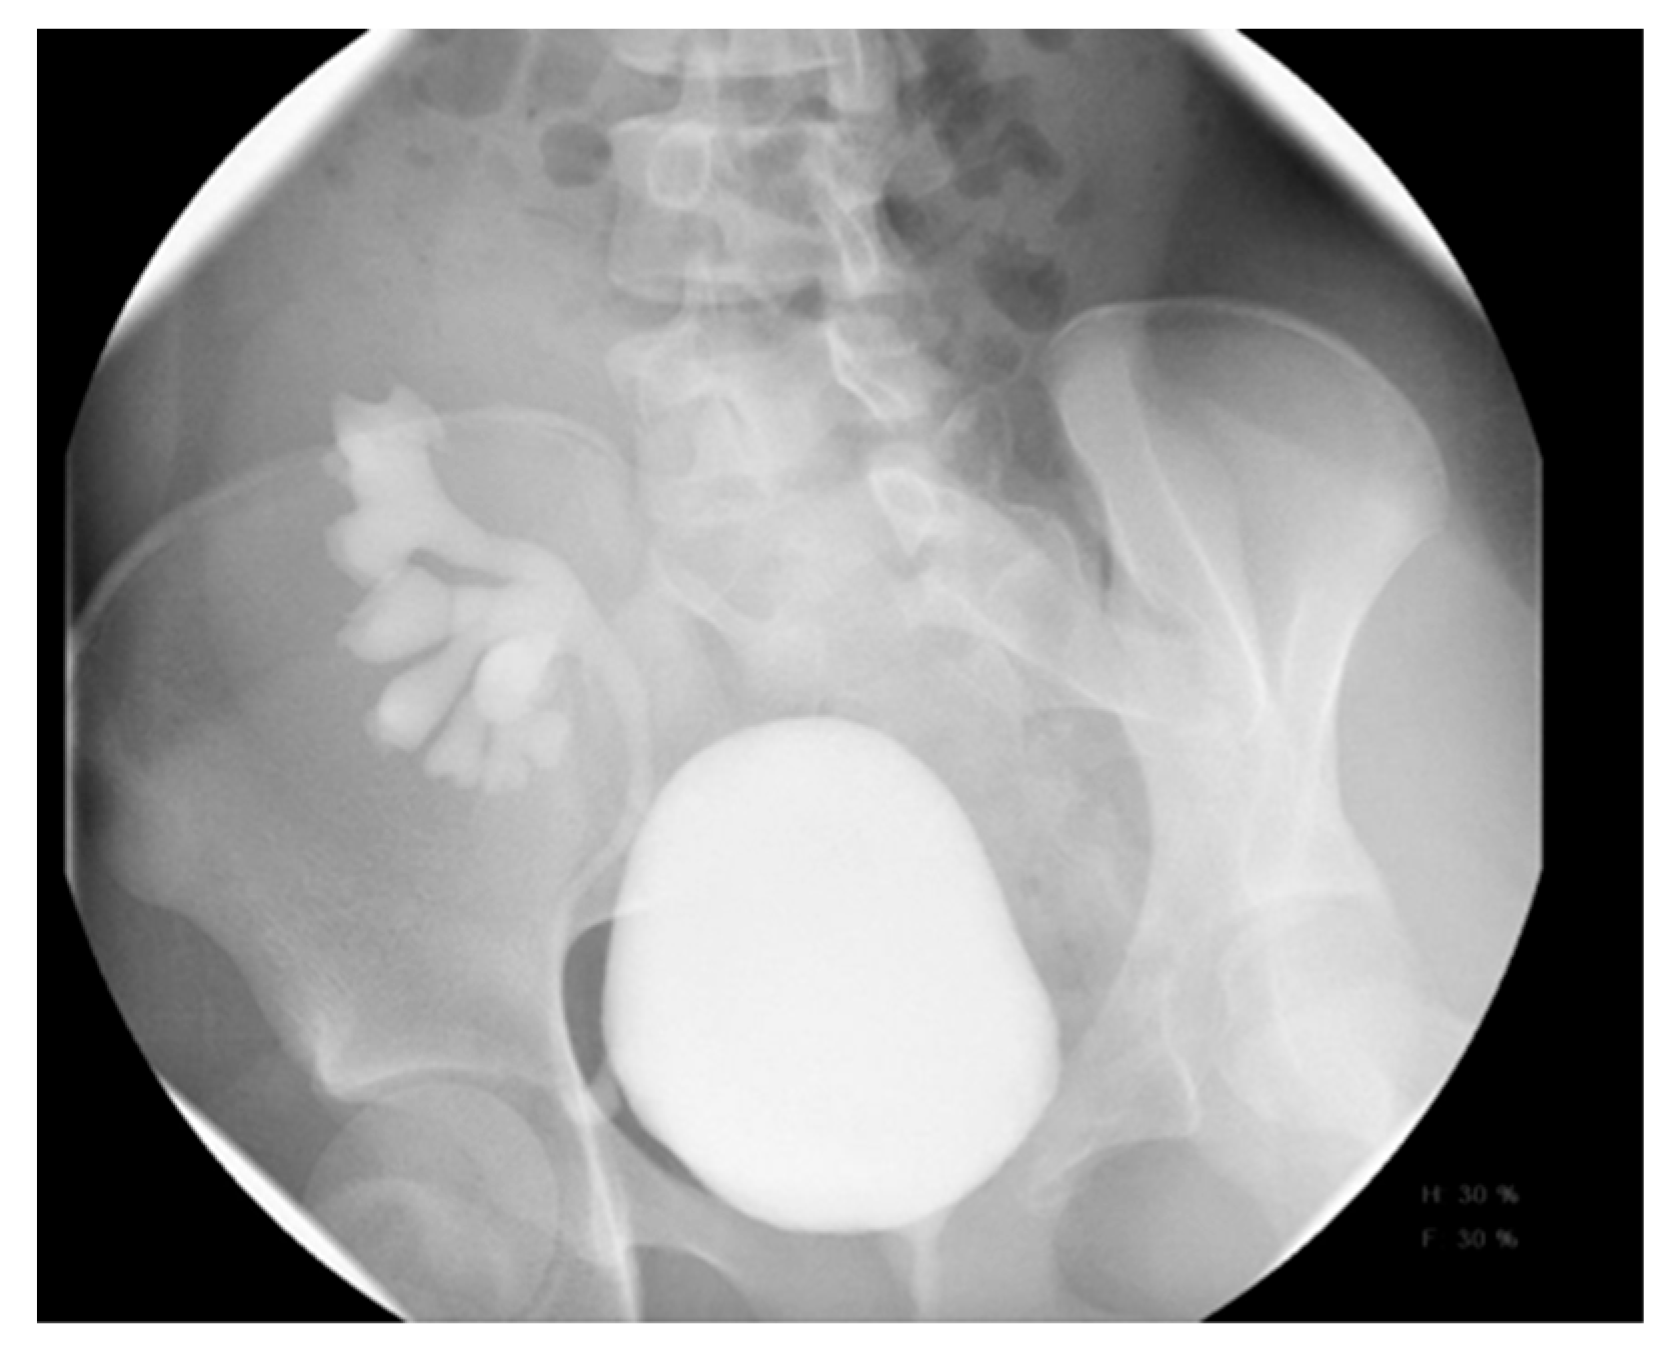

16. Vesicoureteral Reflux